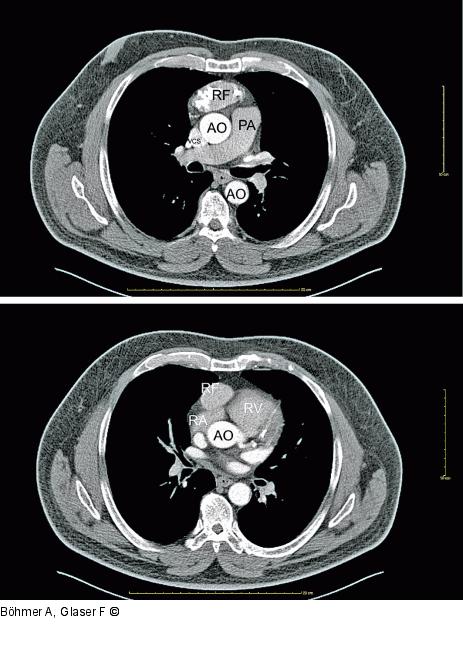

Abbildung 1: CT mit Kontrastmittel CT mit Kontrastmittel: Sagittalschnitt auf Höhe rechte Pulmonalarterie und Einmündung der Vena cava superior in den rechten Vorhof: Arterielle Kontrastphase. Raumforderung im vorderen Mediastinum, mit – abgesehen von den Verkalkungen – ähnlicher Dichte wie der rechte Vorhof. |

CT mit Kontrastmittel: Sagittalschnitt auf Höhe rechte Pulmonalarterie und Einmündung der Vena cava superior in den rechten Vorhof: Arterielle Kontrastphase. Raumforderung im vorderen Mediastinum, mit – abgesehen von den Verkalkungen – ähnlicher Dichte wie der rechte Vorhof. |